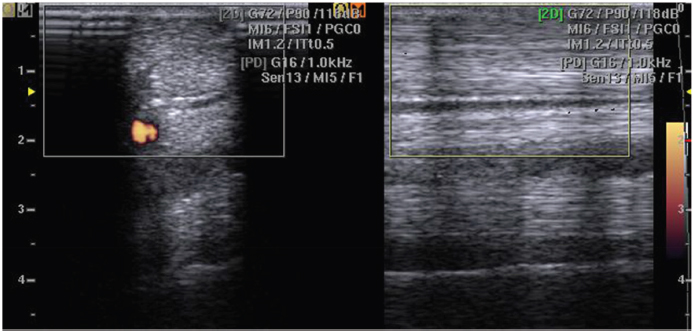

No intratendinous PD signal was detected (PD scores equal to 0) in tendons of horses of group C; only positive PD signal was detectable in intertendinous space (Fig. 1).

Fig. 1. No intratendinous PD signal was detected (PD scores equal to 0) in tendons of horses of group C; only positive PD signal was detectable in interfascicular space. The figure shows typical PD signaling in the normal tendon.

In the normal tendon, the structure is not possible to verify the presence of PD signal within the tendon tissue, but only in the interfascicular zone (Fig. 1). Confirming that in horses, normal tendon shows only sparse vasculature in the interfascicular zone (Smith and McIlwraith, 2012) and verified, both in equine and in human beings species, with the use of CD (de Vos et al., 2007; Kristoffersen et al., 2005) and also by histopathological investigations (Murata et al., 2012).